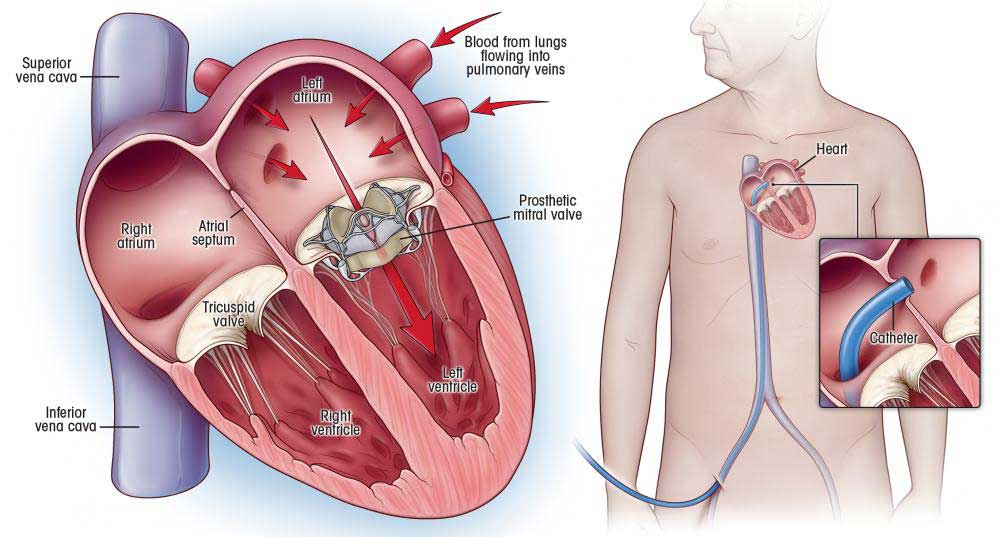

Overview

Package includes:

Days in hospital : 7 to 8 Days (For patient and one attendant)

Days in hotel : 12 Days (For patient and one attendant)

Room type in hospital : Shared

Room type in hotel : Private

Hotel category: General

Value added benefits of the Mitral Valve Replacement:

Ø Doctor consultation charges

Ø Lab tests and diagnostic charges

Ø Room charges inside hospital during the procedure

Ø Surgeon Fee

Ø Cost of implant

Ø Nursing charges

Ø Hospital surgery suite charges

Ø Anesthesia charges

Ø Routine medicines and routine consumables (bandages, dressings etc.)

Ø Food and Beverages inside hospital stay for patient and one attendant.

Extra benefits:

ü Interpreter

ü Visa assistance

Ø Site tourism of the city

Ø Follow up with the doctor

Ø Airport pick up and drop

Ø Free online consultation with the doctor

Ø Priority appointments with the doctor

Ø Room upgrade from sharing to private